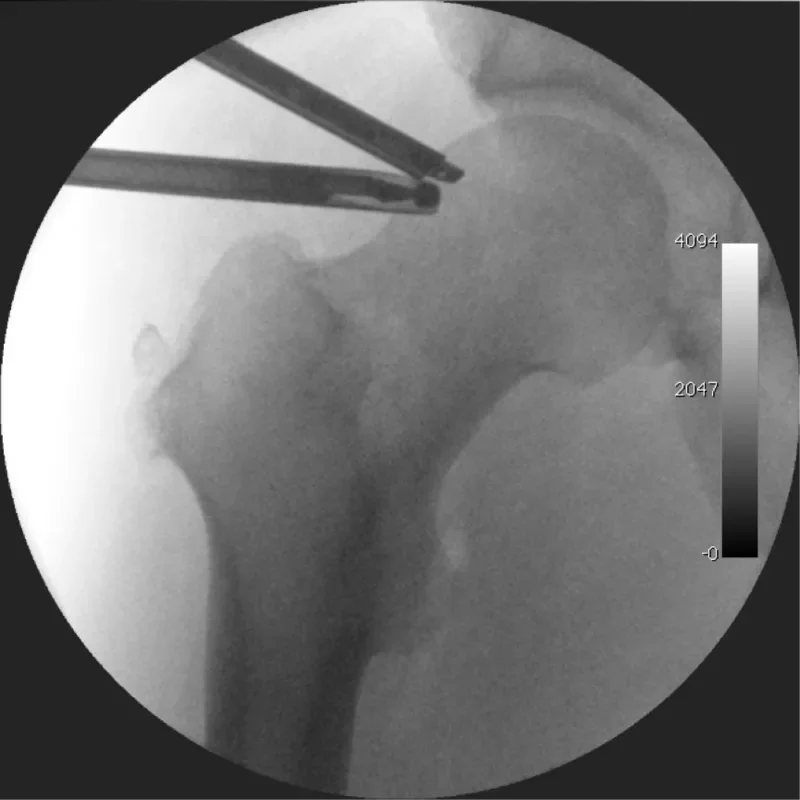

Artroskopija kolka

Artroskopija kolka je minimalno invaziven poseg za diagnostiko in zdravljenje razlicnih stanj kolcnega sklepa.